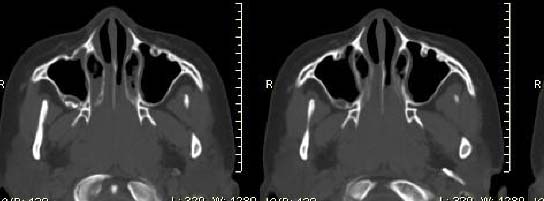

以下是引用随光逐影在2009-6-4 21:13:00的发言:[br]1)考虑鼻咽腺样体重度肥大。2)双侧鼻腔炎性改变。3)双侧上颌窦、双侧筛窦及左侧蝶窦炎症。

以下是引用zsl6918在2009-6-5 7:42:00的发言:[br]首先考虑鼻咽腺样体重度肥大,鉴别纤维血管瘤.强化有助明确.